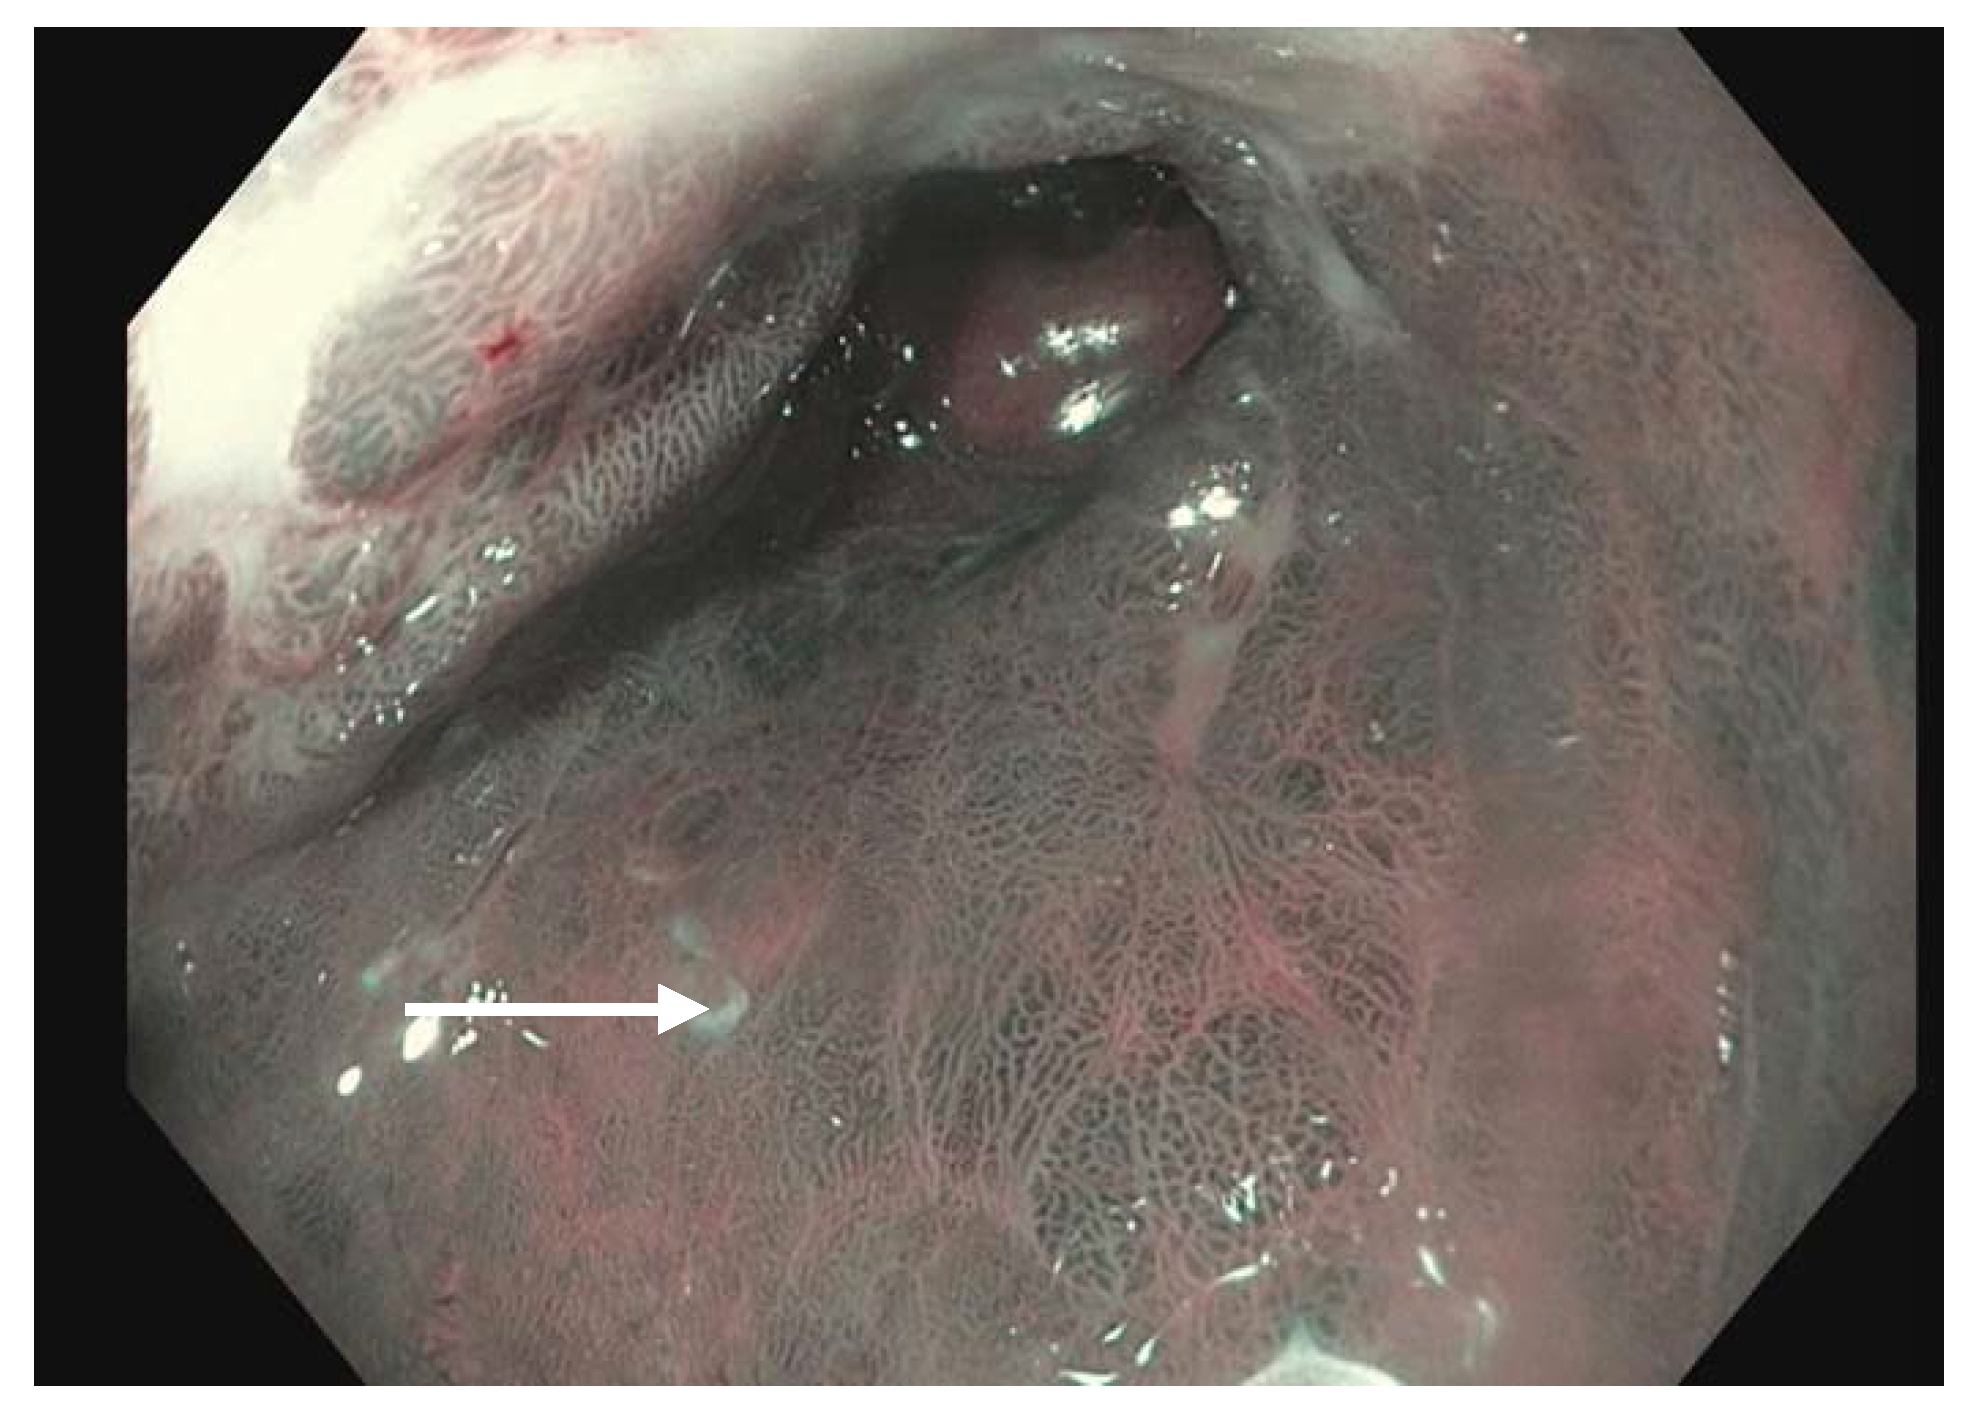

Virtual chromoendoscopy uses technology built directly into the endoscope. The most widely used system is the Olympus narrow band imaging (NBI) (Figure 1) which applies a red–green–blue light filter to maximally highlight the surface mucosa and vascular pattern of the tissue being examined [46]. This narrower spectrum of 400–540 nm (compared to 400–700 nm white light) is matched to the absorption of hemoglobin, causing tissues such as blood vessels and blood to appear darker compared to the surrounding mucosa. Other widely used systems include the Fujinon Intelligent Color Enhancement (FICE) and the Pentax iScan which capture white light images and digitally process them to enhance the surface mucosa and vascular pattern [47]. A meta-analysis of nine studies showed a pooled sensitivity and specificity of greater than 94% each of detecting BE with NBI [48]. A separate study indicated an overall reduction in the number of biopsies while still detecting high-grade dysplasia (HGD) and early adenocarcinoma when white-light and NBI endoscopy were compared [49]. Virtual chromoendoscopy adds no cost, additional time or risk to the patient while providing a useful adjunct during routine endoscopy.

Figure 1.

Narrow band imaging applied to a segment of Barrett’s esophagus (white arrow).